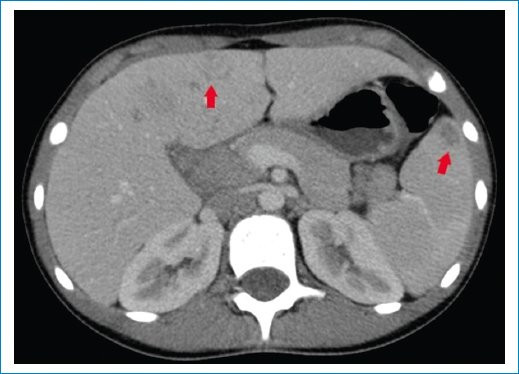

Se trata de una paciente de sexo femenino de 9 años, previamente sana, quien consultó al servicio de guardia pediátrica de nuestra institución por presentar síndrome febril prolongado de 12 días de evolución, sin otro síntoma asociado. A su ingreso, el examen físico reveló buen aspecto general. Se realizó una ecografía abdominal donde se evidenciaron lesiones redondeadas, hipoecoicas, de bordes regulares, que comprometían el parénquima hepático y esplénico (Figs. 1 y 2), las cuales fueron interpretadas como abscesos. Se complementó su estudio con tomografía computada (TC) de abdomen y pelvis con contraste endovenoso, siendo el hallazgo principal la presencia de múltiples imágenes hipodensas con morfología en racimos y realce en anillo tras la administración del contraste endovenoso, distribuidas en el parénquima hepático y esplénico, destacándose la mayor de 29 mm en segmento V hepático (Figs. 3 y 4). Debido a los hallazgos por imágenes y el estado clínico de la paciente, el primer diagnóstico que se planteó fue el de EAG. Se consideraron las lesiones hipodensas múltiples del hígado y bazo como una manifestación importante de enfermedad diseminada o atípica3,5,6. La madre confirmó un gato como mascota, lo cual estaba a favor de nuestra impresión diagnóstica.

Para realizar el diagnóstico de EAG se utilizan pruebas serológicas que detectan la presencia de anticuerpos contra B. henselae4,8. A nuestra paciente se le realizaron pruebas de anticuerpos B. henselae IGG e IGM cuyo resultado fue positivo (1/1.280). Los estudios de imágenes poco aportan ante cuadros de EAG típico, podemos encontrar en la evaluación ecográfica ganglios linfáticos aumentados de tamaño con pérdida de su ecoestructura habitual, generalmente con necrosis central y asociados a edema circundante. Sin embargo, en pacientes con enfermedad atípica o diseminada se han asociado hallazgos característicos que pueden ser útiles para establecer el diagnóstico como la formación de múltiples granulomas hepáticos y esplénicos, con o sin hepatoesplenomegalia, identificados mediante ecografía y TC3. Estos granulomas se identifican inicialmente como lesiones hipoecoicas en ecografía, y en algunos casos presencia de calcificaciones en las fases tardías. En TC presentan características similares a cualquier absceso, hipodensos, redondeados o con morfología en racimos y tras la administración del contraste pueden permanecer hipodensos o mostrar un realce periférico característico. La multiplicidad y el compromiso de varios órganos se relacionan más con infecciones bacterianas, a diferencia de las de origen parasitario, lo cual nos orienta a un mejor diagnóstico.